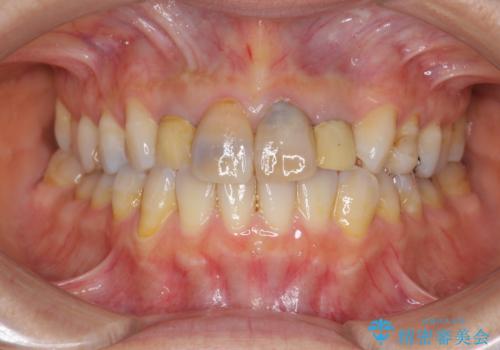

黒ずんだ見栄えの悪い前歯をきれいにしたい

- 「黒ずんで、見栄えの悪い前歯をきれいにしたい。」と、前歯のセラミック治療を希望され来院されました。

全て根管治療のすでになされている歯の変色で、オールセラミッククラウンによる審美性の改善を計画します。